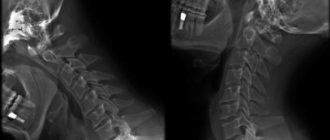

Шейный остеохондроз и зрение: как шейный остеохондроз влияет на глаза Остеохондроз – достаточно распространенная

Нарушение статики позвоночника при остеохондрозе: симптомы и лечение Остеохондроз – это ведущая причина нарушения

Деформирующий остеохондроз: причины, симптомы, лечение Деформирующим остеохондрозом называется мультифакториальное заболевание, которое характеризуется разрушением анатомических